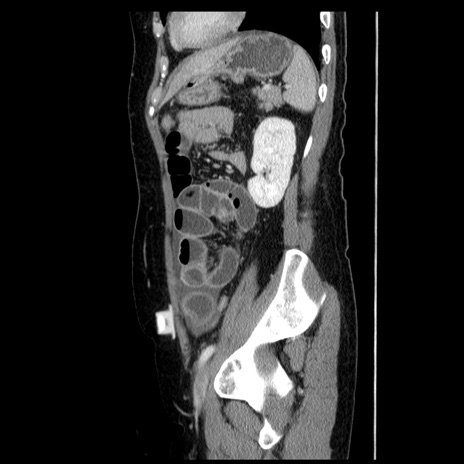

症例6(矢状断像)

【症例】50歳代女性

【主訴】下腹部痛

【現病歴】本日朝より下痢2回あり。 昼食を食べた後、嘔吐3回、下腹部痛認め、症状軽快せず、当院救急搬送。

最終食事:本日昼(生ものなし)。 昨日の夜、刺身を食ぺたとのこと。周囲に同様の症状の者なし。普段、排便は毎日あるとのこと。

【既往歴】卵巣癌術後(8年前に当院で卵巣摘出)

【身体所見】 意識清明、腹部:平坦、腸蠕動音→、やや硬、下腹部自発痛・圧痛あり、反跳痛あり、筋性防御なし。

【データ】WBC 16000、CRP 0.01